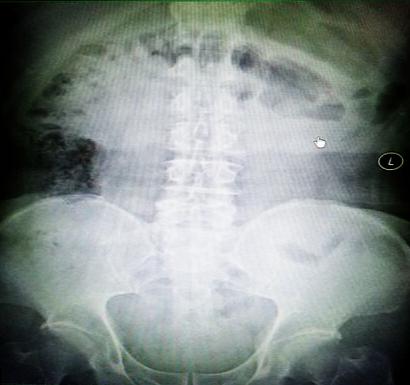

受試患者在結(jié)腸端端吻合術(shù)中,使用我司新研制產(chǎn)品達(dá)到了理想的預(yù)期效果?;颊咝g(shù)后7天、14天X光片顯影,可降解腸道支架均能按研制設(shè)計的預(yù)期時間節(jié)點保持應(yīng)有強度,術(shù)后21天X光片顯示可降解腸道支架已完全破碎,并排出體外。在整個試驗過程中,病患無任何不良反映,耐受良好。